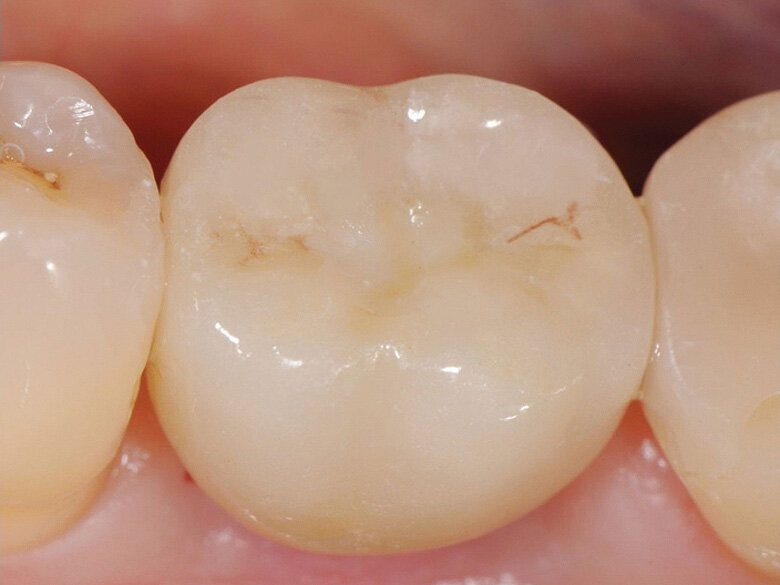

Fig. 12: Crown with composite closure of screw access channel. (Photo: Jens Tartsch, DMD)